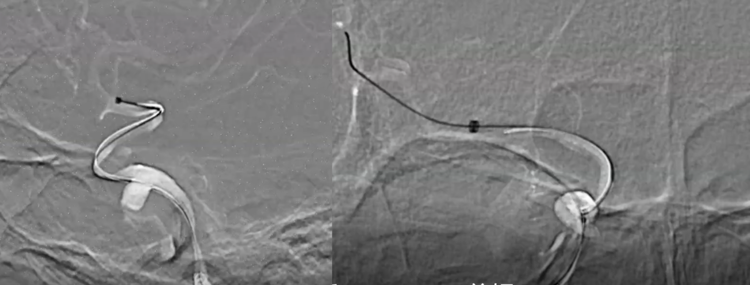

术中Cat5行路图,提示造影剂进入动脉瘤内深部,显示动脉瘤较大,内部血栓是比较新鲜的。

路图下显示XT到位和Cat5到位的情况

Surpass Streamline释放完毕后,未进行按摩和后处理,显示支架打开的完美状态。